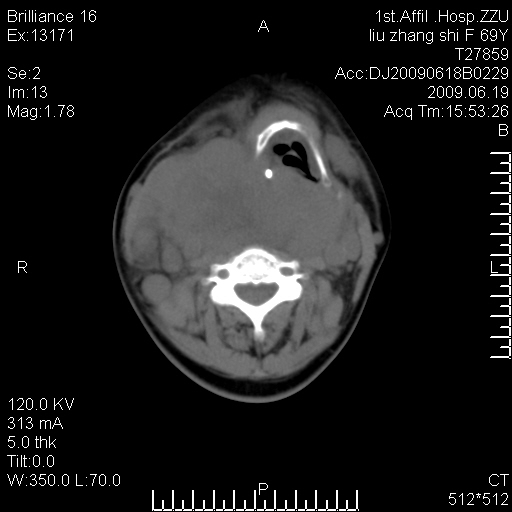

标题: CT26782:女,69岁,颈部占位,3天后公布病理结果。

【病理证实系列】女,69岁,颈部占位,有病理结果,3天后公布。(由于病例时间较久,临床资料不全,请网友见谅)本系列将有几百种常见、少见及罕见病例,均经病理证实。病例资料来自郑州大学第一附属医院。与网友共享,本人有空就发。

甲状腺癌并颈部淋巴结转移。感谢楼主的良苦用心,谢谢。

甲状腺癌并颈部淋巴结转移。

需与鼻咽癌鉴别!

支持甲状腺癌广泛侵及周围结构并颈部淋巴结转移。

鉴别:淋巴瘤、恶性神经源性病变、恶性纤维组织细胞瘤。

病理结果:颈部非霍奇金淋巴瘤。

右侧甲状腺确实有问题